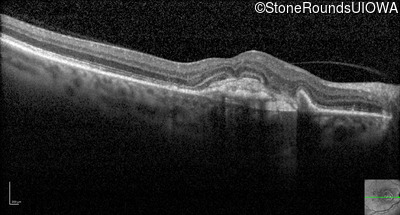

Optical Coherence Tomography - Right - 20/200 +1

Exemplar / OCT Stack

Infrared Fundus Photograph - Right - 20/200 +1